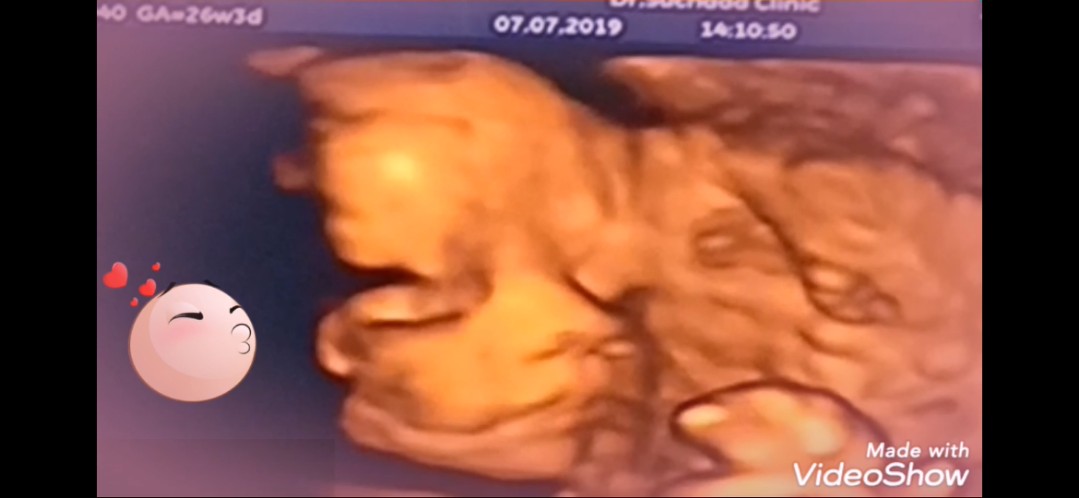

ตอน 26สัปดาห์ค่ะ เพศชาย